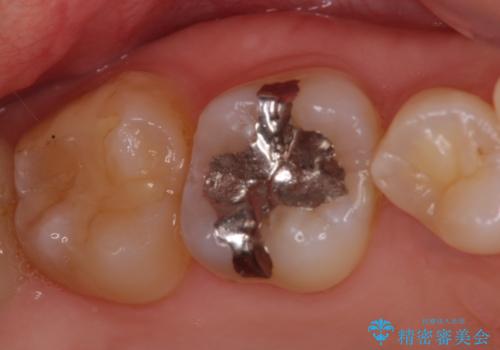

- 奥歯の虫歯と前歯のデコボコや突出感を気にして来院された患者様です。

矯正治療後は、奥歯の虫歯や銀歯を補綴・修復治療することとしました。